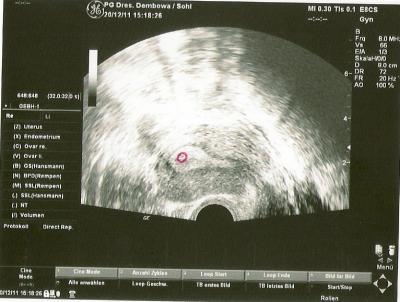

Hallo ihr Lieben, ich hatte dann doch kurzfristig heute meinen 1. FA Termin. Bin noch ganz am Anfang in der 5. SSW (4+3). Auf dem Ultraschall ist es minimal zu sehen oder zu erahnen als Laie . Ich stell es einfach mal mit rein, da ich ja so stolz auf unser Krümelchen bin, sein 1. US Bild. Lieben Gruß Sallymaus

Bild zu Vom 1. FA Termin zurück - Forum für August - Mamis